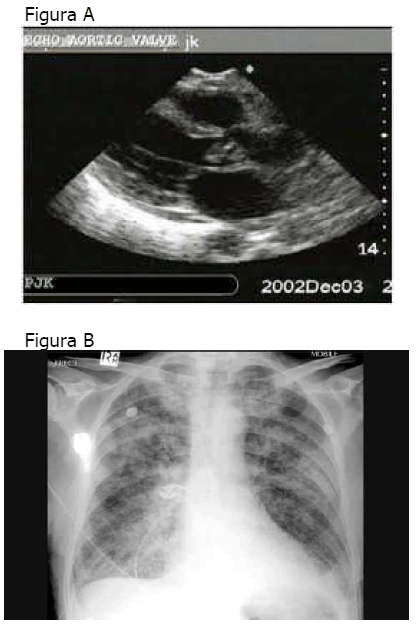

Paciente, 40 anos, apresenta febre há dez dias e início de dispneia há quatro dias. No exame físico, a PA era 90/60mmHg e a FC era 110bpm. Na ausculta cardíaca, apresenta sopro diastólico. O ecocardiograma transtorácico e o Rx de tórax estão representados nas figuras A e B, respectivamente.

Assinale a alternativa que apresenta o melhor manejo para o caso acima referido.